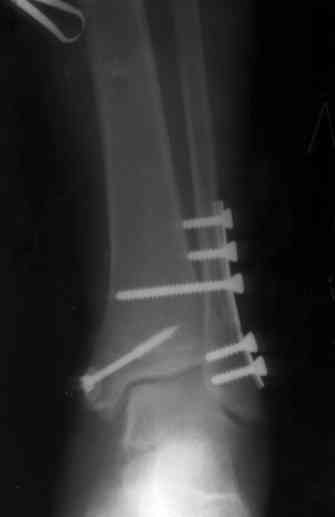

Здесь финальный снимок 73 летней с

сопутствующей шизофренией, латерально бридж

пластину (соединили дистальный конец с диафизом не трогая место перелома) и медиально перкутанно

двумя шурупами. В этам случае без гипса не

обойтись.